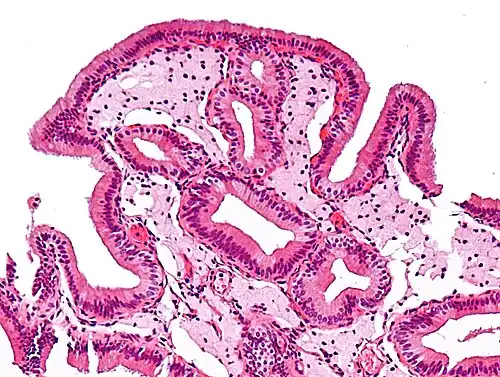

Micrograph of cholesterolosis of the gallbladder, with an annotated foam cell. H&E stain.

The name strawberry gallbladder comes from the typically stippled appearance of the mucosal surface on gross examination, which resembles a strawberry. The term was coined by surgical pathologist William C. MacCarty of the Mayo Clinic in 1910.[2] Cholesterolosis results from abnormal deposits of cholesterol esters in macrophages within the lamina propria (foam cells) and in mucosal epithelium. The gallbladder may be affected in a patchy localized form or in a diffuse form. The diffuse form macroscopically appears as a bright red mucosa with yellow mottling (due to lipid), hence the term strawberry gallbladder. It is not tied to cholelithiasis (gallstones) or cholecystitis (inflammation of the gallbladder).[3]